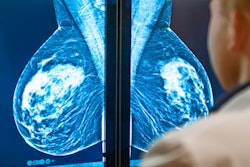

Like anticancer treatments, screening mammography grew into prominence in the 1970s after successful clinical trials, the researchers noted. Technological improvements have led to modern mammography systems that are more effective with less radiation.

Since the start, breast screening has had the goal of minimizing late-stage cancer diagnoses in order to maximize the amount of time anticancer treatments have to work, according to the authors. In this way, it should be obvious why improved mammography and personalized anticancer treatments work in tandem to improve breast cancer outcomes.

Trimboli and colleagues pointed to a number of studies showing the role screening mammography plays in improved cancer outcomes, but perhaps the strongest argument was that a patient's stage at diagnosis is still one of the top factors for predicting their odds of surviving breast cancer.